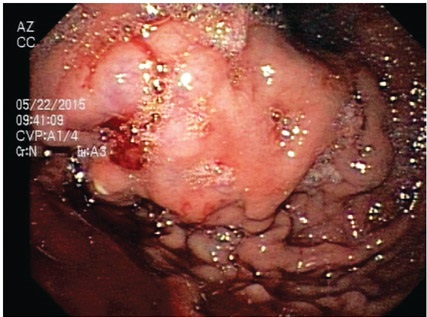

Puncionar la várice e inyectar entre 1 y 3 mL de la mezcla, seguidos de agua destilada en la cantidad previamente establecida de acuerdo con la medición del espacio muerto. Se pueden infiltrar una o varias várices (figura 3).

La punción se debe realizar en proximidad al punto rojo o punto de sangrado en caso de existir. Se debe observar cómo la várice se distiende al inyectar la mezcla, tornándose posteriormente firme a la compresión con el catéter.